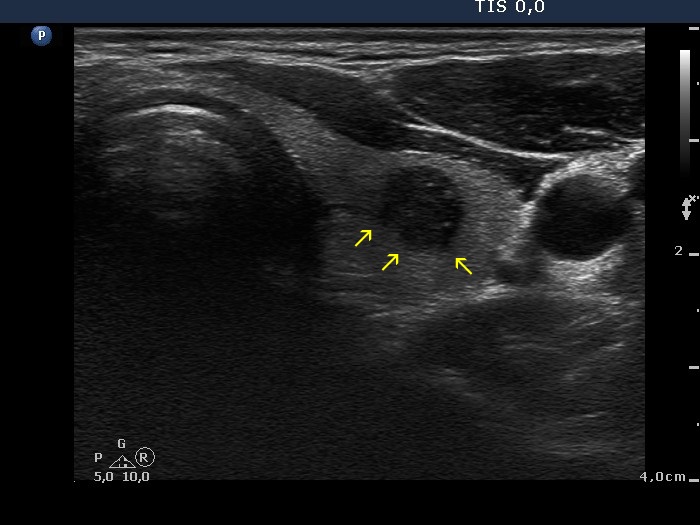

100 consecutive cases of papillary cancer - case 034 (ultrasonographic picture 3b)

Left lobe, transverse scan. The yellow arrows point to lobulated margins.